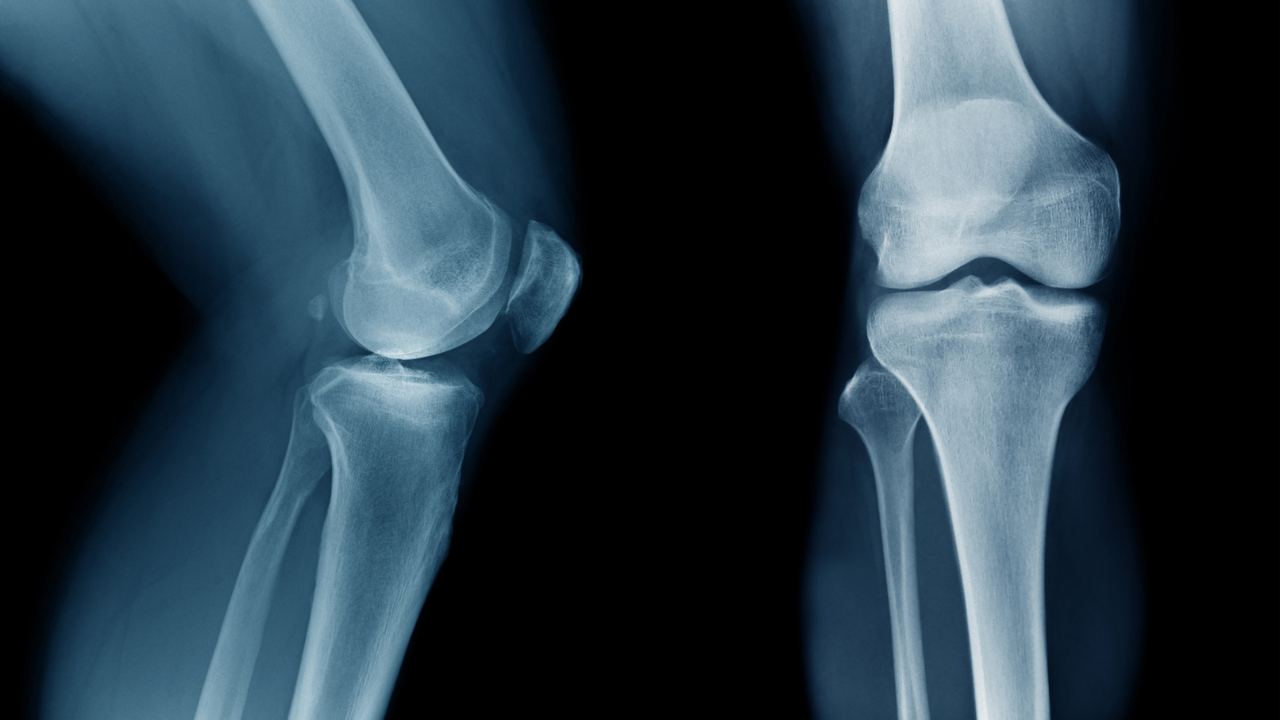

X-ray

Useful for assessing bone structure, joint alignment, and degenerative changes such as arthritis. It is often the first step when bony pathology is suspected.